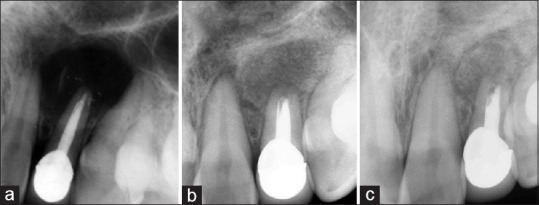

Figure 3.

(a) Intraoperative radiograph (radiovisiography). (b) 3rd month radiograph. (c) 6th month radiograph of a patient treated with decalcified freeze-dried bone allograft

Figure 4.

(a) Intraoperative radiograph (radiovisiography). (b) 3rd month radiogragh. (c) 6th month radiograph of a patient treated without bone graft